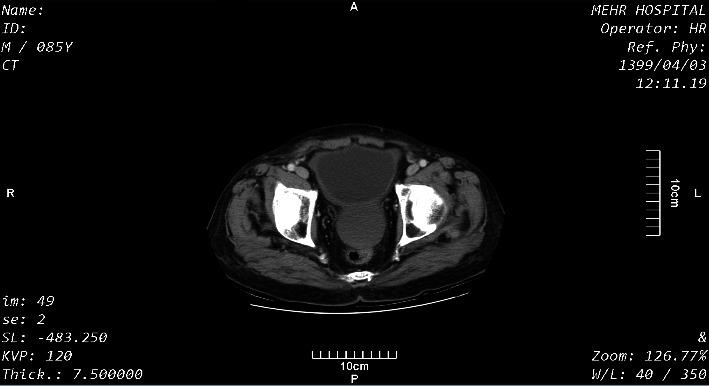

Echinococcosis is a zoonotic infection caused by species. Iran is endemic for . Here, we present a case of hydatidosis in an 85-year-old man, presented with acute, dull, constant, and generalized abdominal pain. A computed tomography scan (CT scan) showed an intact hydatid cyst on the bladder dome and several hydatid cysts in the liver. Open surgery revealed a cyst with hepatic origin, confirmed with histopathological studies.

包虫病是由某些物种引起的一种人畜共患感染。伊朗是[具体包虫种类]的地方病流行区。在此,我们报告一例85岁男性的包虫病病例,该患者表现为急性、钝痛、持续性全腹痛。计算机断层扫描(CT扫描)显示膀胱穹窿部有一个完整的包虫囊肿,肝脏有多个包虫囊肿。开放手术发现一个源于肝脏的囊肿,经组织病理学研究得以证实。